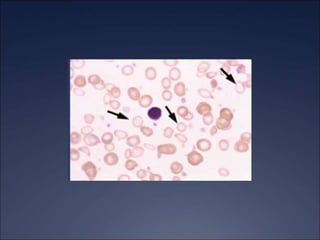

Iron Deficiency Anemia: Peripheral

Microcytosis &, Hypochromic RBCs

• #42 The arrows show that the RBCs are smaller and paler